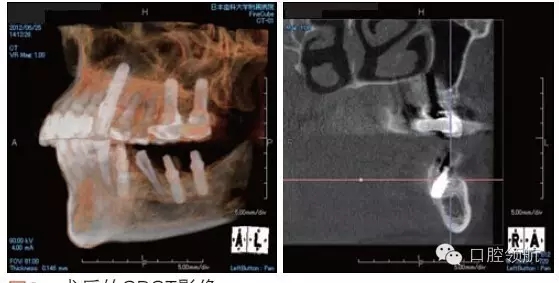

利用曲面斷層及CBCT檢查埋入部位情況,雖未出現(xiàn)與主訴相關(guān)的神經(jīng)損傷,但無意中卻發(fā)現(xiàn)了種植體的舌側(cè)穿孔(圖1、圖2)。

圖2 術(shù)后的CBCT影像。

雖不能確定是裂鉆備洞還是植入種植體所造成的穿孔,但從4個月的病情的發(fā)展看,考慮可能是術(shù)中的舌下動脈損傷導致口底軟組織內(nèi)出血而造成的感覺異常。采用常規(guī)藥物及物理療法開始進行治療。